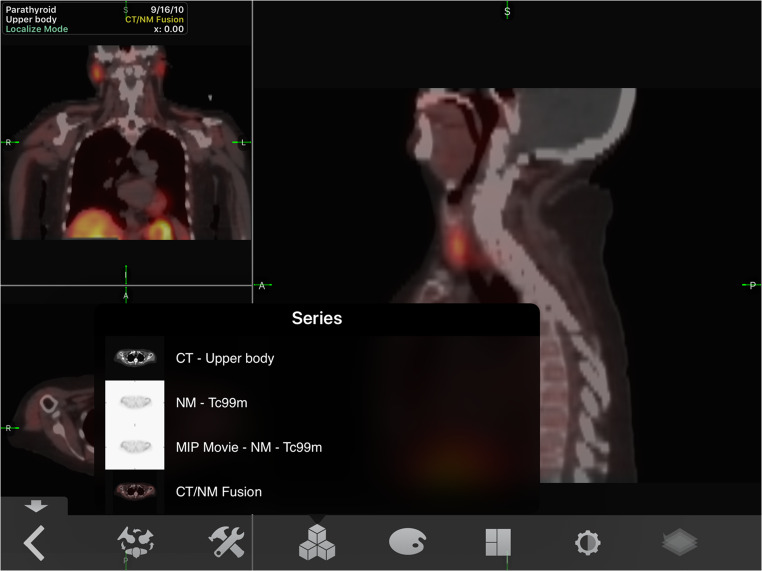

For example, Sample_H7 was a SPECT/CT for parathyroid adenoma and the user can examine only the CT, only the nuclear medicine scan, and the CT/NM fusion (Fig. 1).2. Layouts

Fig. 1.

Series of sample_H7. SPECT/CT image set for parathyroid adenoma. The figure demonstrates the tool that allows the user to manipulate scans from the individual modalities, play an image progression of the nuclear medicine scan, and examine the CT/NM fusion